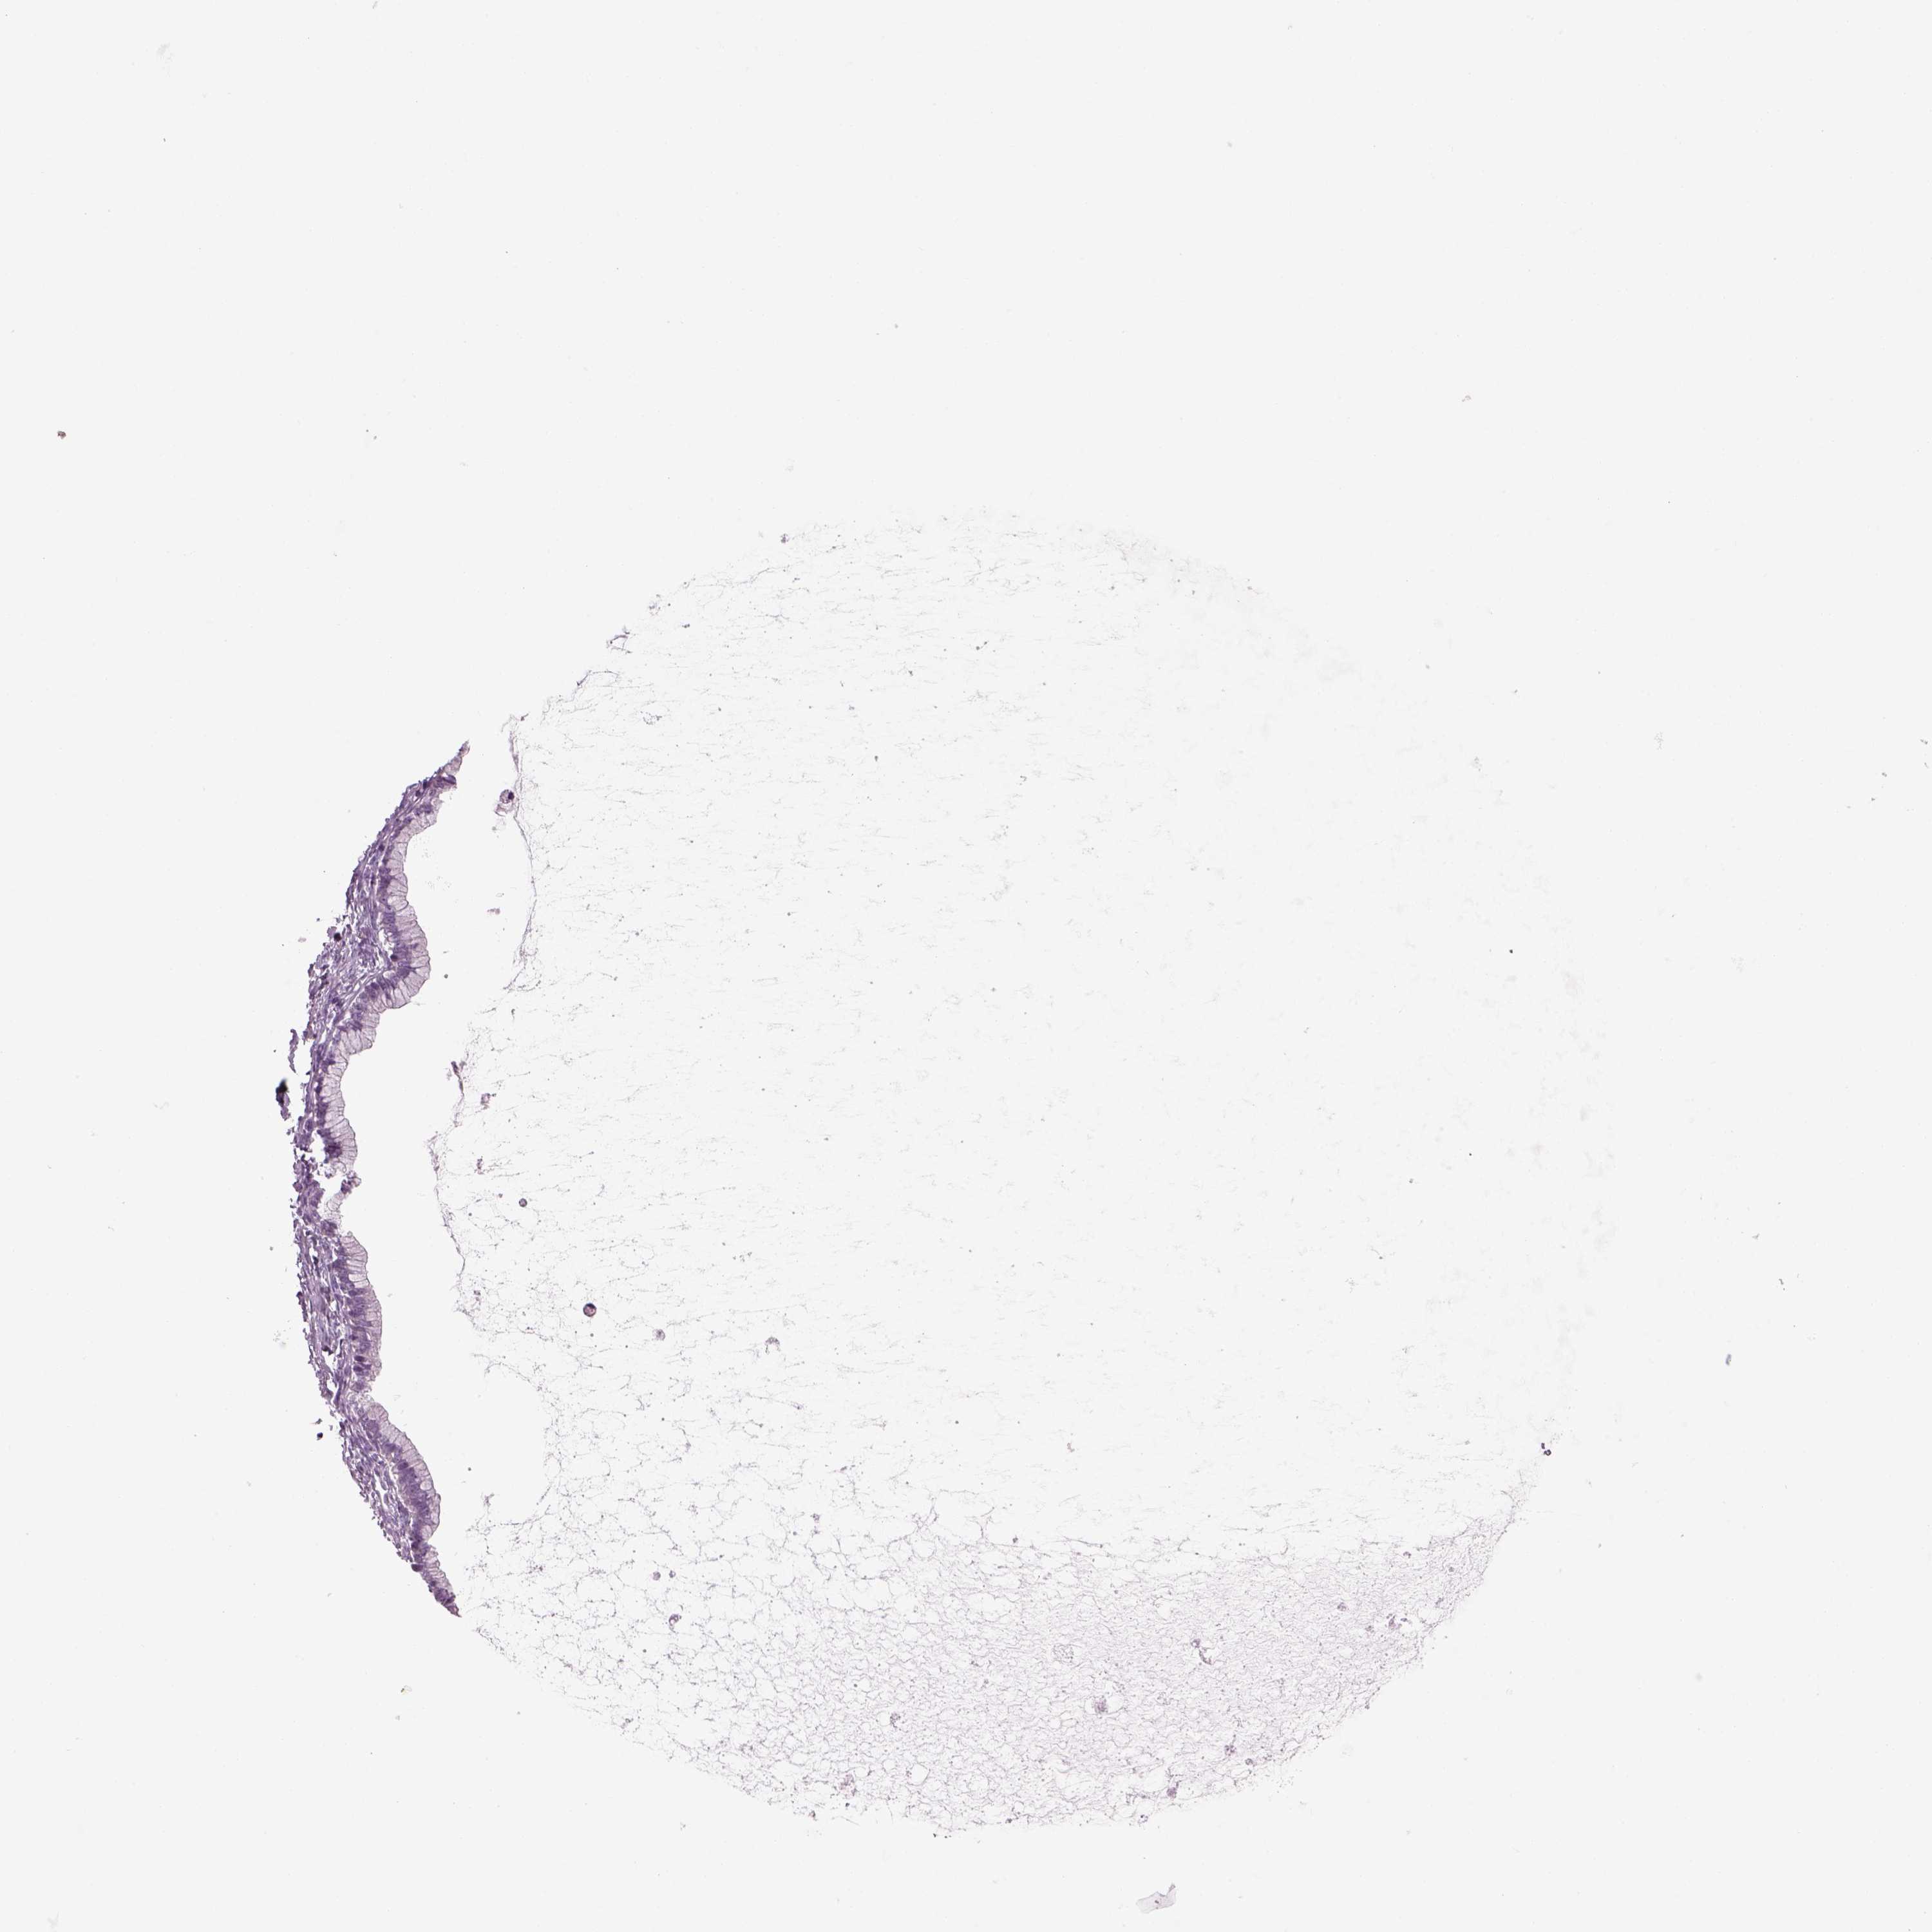

OVARIAN CANCER - Protein expressioni

A mouse-over function shows sample information and annotation data. Click on an image to view it in a full screen mode. Samples can be filtered based on level of antibody staining by selecting one or several of the following categories: high, medium, low and not detected. The assay and annotation is described here.

Note that samples used for immunohistochemistry by the Human Protein Atlas do not correspond to samples in the TCGA dataset.

Antibody stainingi

Antibody staining in the annotated cell types in the current human tissue is reported as not detected, low, medium, or high, based on conventional immunohistochemistry profiling in selected tissues. This score is based on the combination of the staining intensity and fraction of stained cells.

Each image is clickable and will lead to virtual microscopy that enables deeper exploration of all samples and also displays staining intensity scores, fraction scores and subcellular localization as well as patient and tissue information for each sample.

Antibody HPA073761

Staining

High

Medium

Low

Not detected

Intensity

Strong

Moderate

Weak

Negative

Quantity

>75%

75%-25%

<25%

None

Location

Nuclear

Cytoplasmic/membranous

Cytoplasmic/membranous,nuclear

Cystadenocarcinoma, serous, NOS

Cystadenocarcinoma, mucinous, NOS

Carcinoma, endometroid